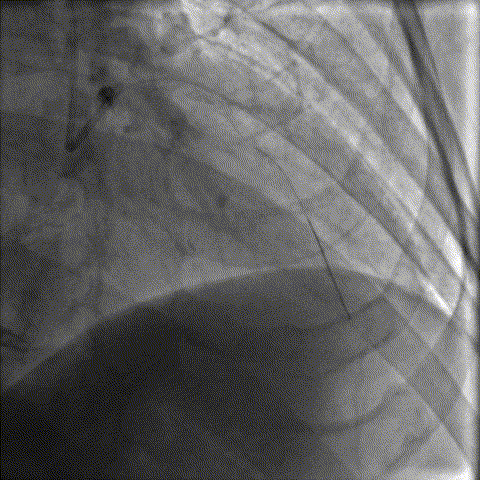

干预LAD,重度钙化伴迂曲

Sion导丝,Sprinter2.0/20预扩张,但Cutting Balloon2.0/10不能通过病变部位,后在Telescope™导引延长导管支撑下成功到位。

DCB2.0/20顺利到位,成功扩张